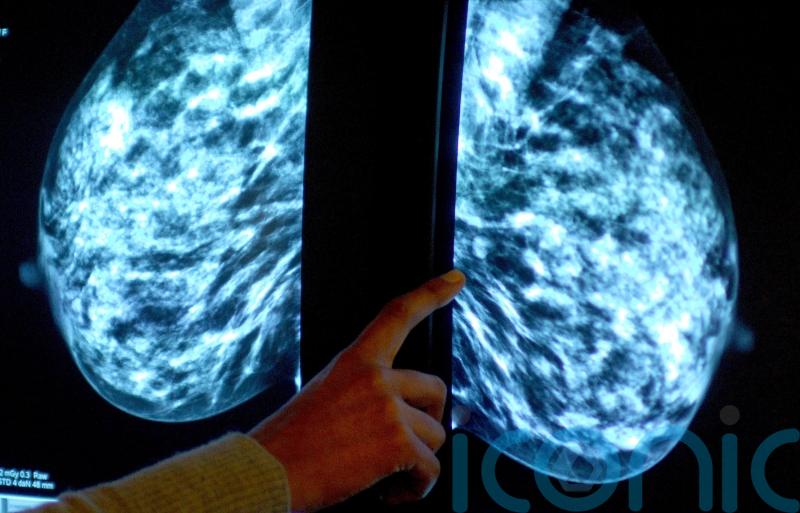

Immune cell discovery ‘could lead to personalised treatment for breast cancer’

Scientists have found that some immune cells hunt down cancer in the body, a discovery that could lead to personalised treatments for advanced breast cancer.

The study identified features of cells called immune B cells which make them successful at targeting tumours, including when cancer has spread to a different part of the body.

Researchers have developed a tool to identify these anti-cancer cells which could lead to improved, personalised immunotherapies, they say.